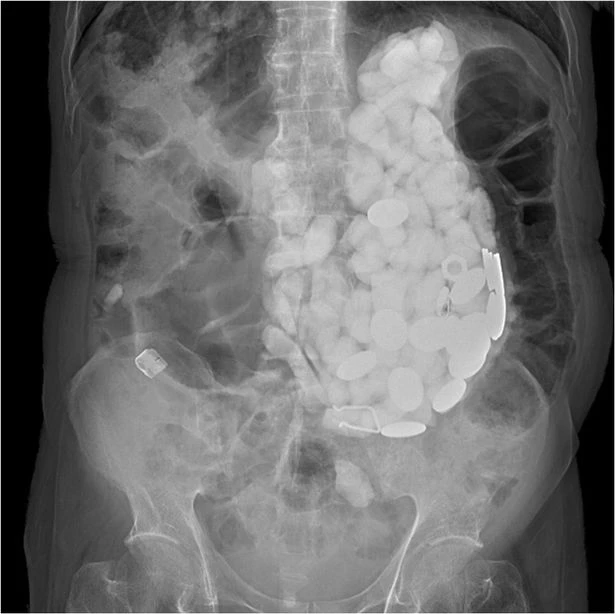

Đá sỏi, nắp chai và tiền xu được lấy ra từ dạ dày của người đàn ông.         Ảnh:  AMERICAN JOURNAL OF MEDICAL CASE REPORTS

Sau khi xét nghiệm cho thấy có số lượng lớn vật thể “chiếm phần lớn thể tích dạ dày” của bệnh nhân.

Các bác sĩ hoàn toàn chết lặng khi họ tìm thấy một khối bao gồm hàng chục dị vật. Đá sỏi, nắp chai và tiền xu có tổng khối lượng là 2kg được lấy ra từ trong dạ dày của người đàn ông.